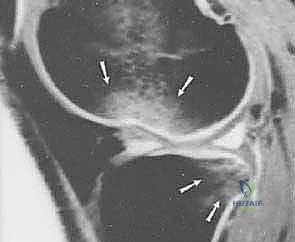

- التصوير بالرنين المغناطيسي (MRI): هو المعيار الذهبي لتأكيد التشخيص. الرنين المغناطيسي لا يظهر الرباط المتمزق فحسب، بل يُظهر الإصابات المصاحبة التي لا تقل أهمية، مثل:

- تمزق الغضاريف الهلالية (Meniscal tears).

- كدمات العظام (Bone bruises) التي تحدث نتيجة ارتطام عظم الفخذ بالقصبة لحظة الإصابة.

- إصابات الأربطة الجانبية.